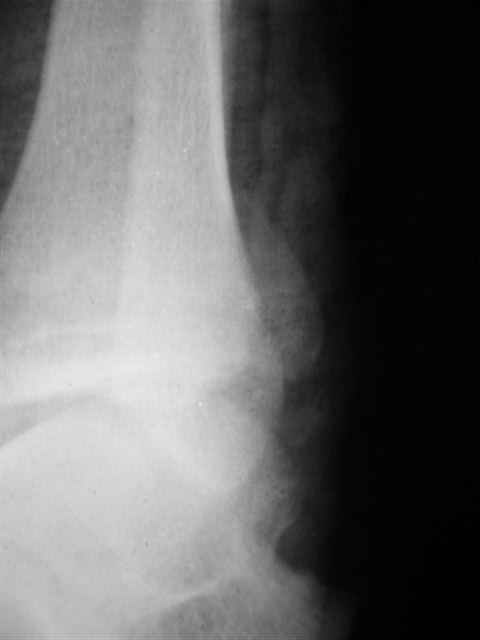

А можно,пожалуйста, более конкретно про повреждение голеностопного сустава?

В первом письме я упомянул о закрытом повреждении правого голеностопного сустава, эверсионно-пронационный механизм травмы - перелом внутренней лодыжки( поперечный, на уровне суставной щели) и отрывной перелом бугорка Chaput. После обработки открытых переломов бедра и большеберцовой кости в эту же сессию перелом внутренней лодыжки фиксировал двумя расходящимися спицами, бугорок Chaput двумя тягловыми винтами 3,5 мм. Раны заживают благополучно. Учитывая повреждение наружной группы мышц, активное разгибание в голеностопном суставе ограничено. Пассивная + пассивно-активная мобилизация голеностопного сустава с физиотерапевтом.

Каких-либо вопросов по лечению травмы голеностопного сустава у меня не возникло,поэтому о дальнейших деталях лечения я не упоминал.

(Если вы заинтересовались, то Рг граммы представлю)

Уважаемый Иван,

Я предупреждал, что ничего сверхъестественного. Каюсь, что одна из спиц прошла несколько дальше, чем нужно было, но главное - перелом стабилизирован и больной работает суставом в полном объёме, несмотря на представленную раннее травму коленного сустава.